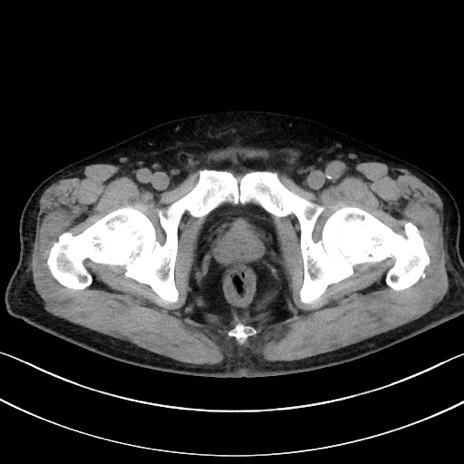

症例15(横断像)

【症例】70歳代男性

【主訴】腹痛

【現病歴】今朝から腹痛あり。全体的に痛い。特に左上の方。排ガスが今日はない。冷や汗が出る。

【既往歴】直腸癌術後

【身体所見】左側腹部〜上腹部に圧痛あり。腹膜刺激症状明らかなではない。軽度反跳痛。左下腹部に術後瘢痕あり。

【データ】WBC 7700、CRP 0.02